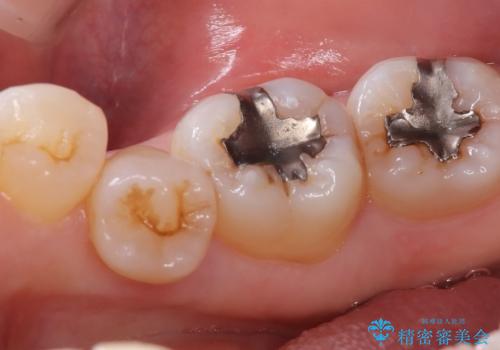

- 主訴:口を開けると所々入っている銀の詰め物が目立つので白い物にやり替えたい。

下顎大臼歯部に入っている保険適用のメタルインレーを、適合性と審美性の良いセラミックインレーでのやり替えとなりました。